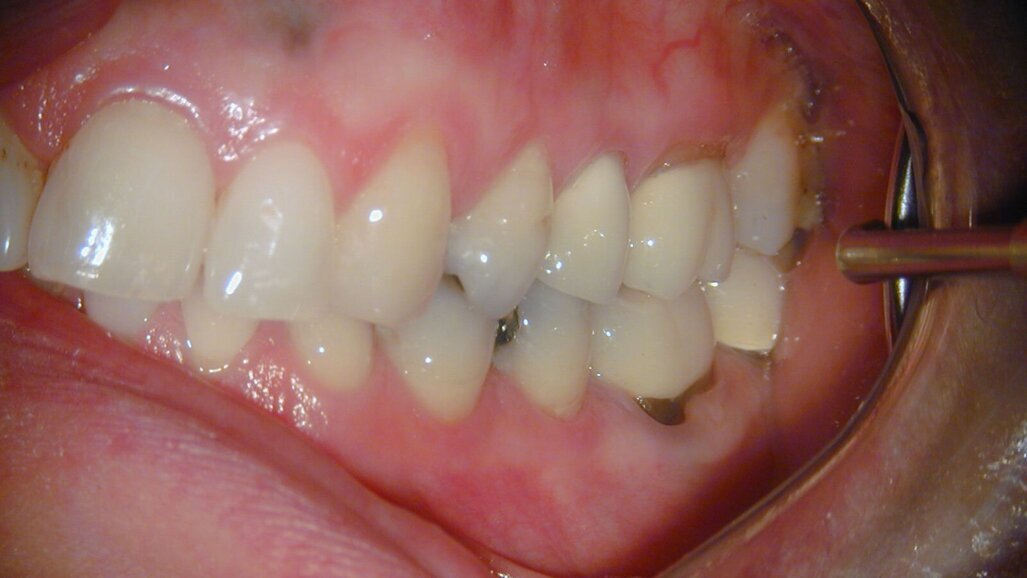

Een 23-jarige vrouw meldde zich bij mij in de praktijk met een pijnklacht aan de 36. Het element was sinds een paar dagen pijnlijk met koud, en intra-oraal onderzoek kon de klachten van de patiënt reproduceren. Röntgenologisch was een diepe amalgaamrestauratie met een para-pulpaire pin zichtbaar (afb. 1). De diagnose luidde een irreversibele pulpitis, en na het toedienen van lokale anesthesie werd het element onder rubberdam gebracht en werd een endo ingezet.

Afb. 1: Bitewing van het tweede en derde kwadrant